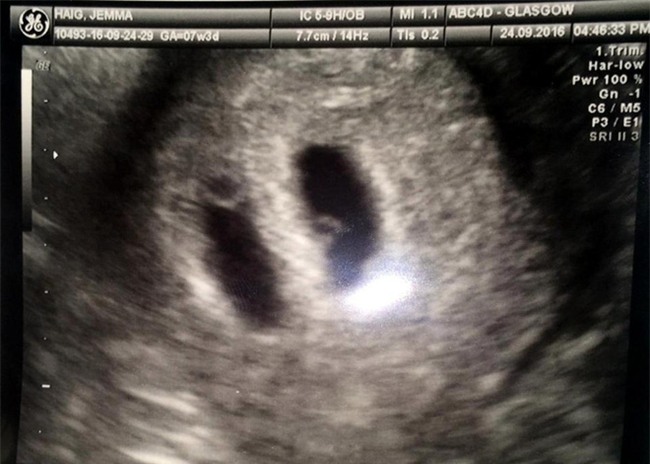

Bác sĩ phát hiện cô Jemma mang hai túi ối. (Ảnh: Thesun)

Được biết, trước đó cô Jemma đã làm cuộc kiểm tra thai định kì như những sản phụ khác thì bất ngờ phát hiện cô đang mang hai túi nước ối, một túi chứa phôi của con trai Thomas, và một túi còn lại chứa phôi của cặp song sinh dính liền. Thường các cặp song sinh này có chung một trái tim, có chung hệ hô hấp và hệ tiêu hóa. Và trường hợp này được xem là khá hiếm hoi. Jemma nói rằng cô không muốn các con phải chịu đựng, cô giải thích: “Chúng tôi sẽ đưa ra quyết định cuối cùng, tôi không muốn hai con song sinh phải chịu đau khổ. Chúng tôi cũng biết rằng việc này mang lại rủi ro sẩy thai khá cao, nhưng dù sao cũng hy vọng và cầu nguyện rằng mọi thứ sẽ tốt đẹp”.